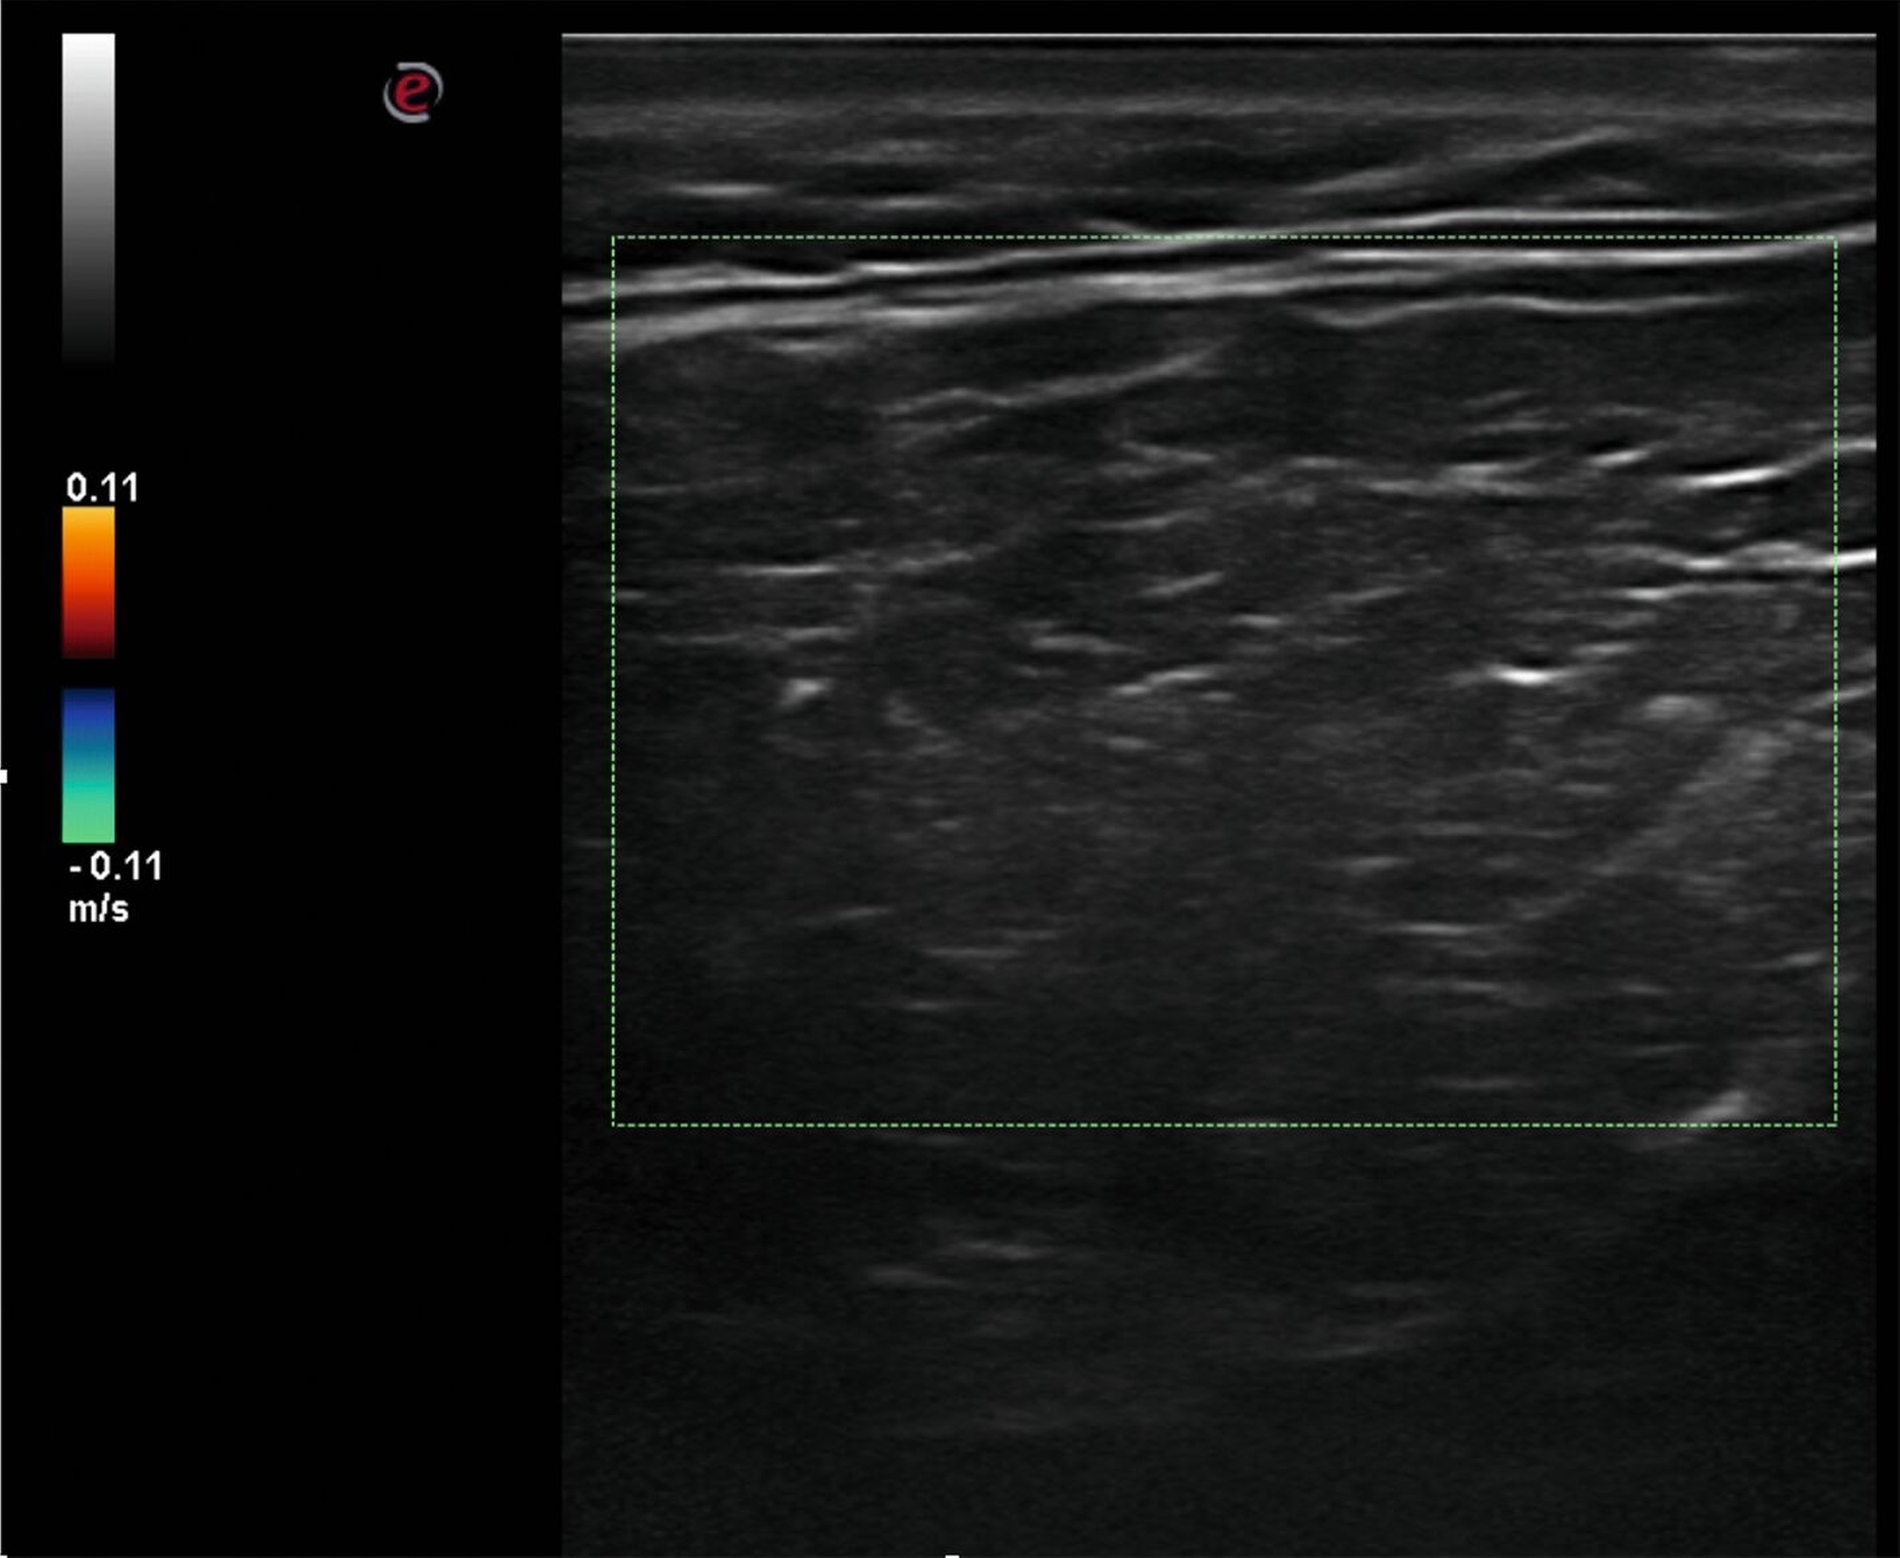

Die klinische Untersuchung zeigte einen verschieblichen, weichen und nicht druckdolenten Befund, der bereits zu einer sichtbaren Volumenzunahme der linken Halsseite geführt hatte (Abbildung 1). Zur erweiterten Diagnostik erfolgte eine Sonografie, in der sich ein Befund mit gefiedertem Binnenecho darstellen ließ (Abbildung 4). Malignitätszeichen fanden sich auch zu diesem Zeitpunkt weiterhin nicht. Es wurde die Verdachtsdiagnose eines Lipoms gestellt.